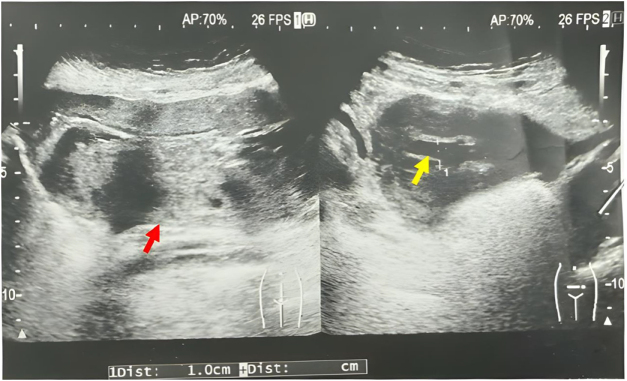

Case presentation: We report the case of a 25-year-old woman with a twin pregnancy who was admitted at 32 weeks of gestation with acute abdominal pain and nausea. Due to persistent severe pain, unexplained intraperitoneal fluid, and progressing labor, an emergent cesarean section was performed. Intraoperatively, 2000 mL of milky white fluid was discovered in the peritoneal cavity. Biochemical analysis with markedly elevated triglycerides confirmed the diagnosis of chylous ascites. Postoperative management included broad-spectrum intravenous antibiotics, octreotide injection, and a low-fat diet supplemented with medium-chain triglyceride oil. By postoperative day 7, ultrasound showed complete resolution of ascites, and the patient was discharged in stable condition. No recurrence was noted during 3 years of follow-up.